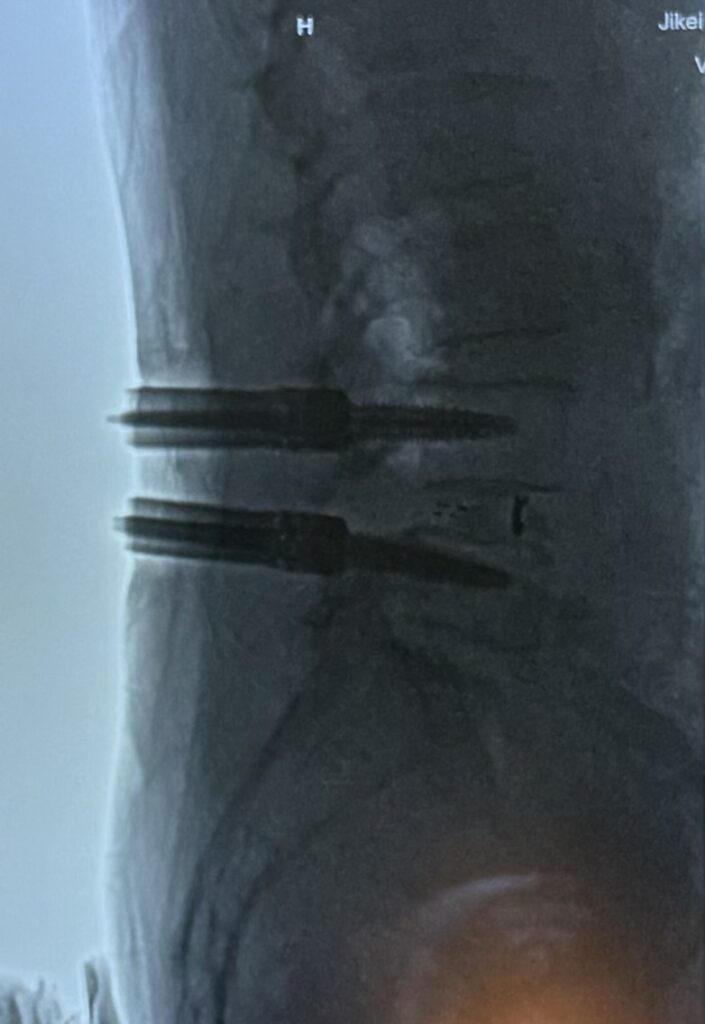

今回は椎間関節を削って除圧し、非常にスマートに椎間板にアプローチし、両側からケージを挿入し、椎体にスクリューを挿入し、後方固定を追加しました。当時やっていた脊柱管の拡大作業はあまりせずとも辷りを矯正すると狭窄症が治るとのことでした。たしかにそうですけど、昔は良いデバイスもなかったのでできない手術でした。

赤いと刺激的なので白黒にしていますが、傷からスクリューが4本入ったところ。

その場でレントゲン確認したところ。これで固定していきます。椎間関節を削る=後方固定が必須ということです。